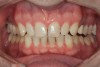

A 34-year-old male patient with no medical issues presented to the office with the chief complaint of a failing crown on tooth No. 12. The patient was also unhappy with his bite and the appearance of his teeth (Figure 1 and Figure 2).

A comprehensive examination was carried out, and preoperative photographs were taken (Figure 1 through Figure 4). The patient presented with fair oral hygiene and slight, generalized tissue inflammation. Caries and defective restorations were detected on teeth Nos. 4, 5, 13, and 14. The crown on tooth No. 12 was showing signs of leakage, and although the endodontic access cavity had been temporarily restored with composite, this endodontic re-treatment was acceptable and the tooth was otherwise symptom-free. Erosion was present on most of the posterior teeth and the cuspids, and abrasion was noted on teeth Nos. 4, 5, 10, 11, 20, 21, 22, 28, and 29. An examination of the patient's muscles, joints, and bite revealed no joint sounds, a normal range of motion, and negative joint load and immobilization tests.

The dentofacial examination revealed a low smile line with no incisor display when the lips were in repose. The anterior teeth were chipped and worn, and their overall color was darkened. The buccal corridors were deficient, and the failing crown on tooth No. 12 was visible in a full smile.

(1.) Preoperative smile photograph.

Figure 1

(2.) Preoperative retracted view.

Figure 2